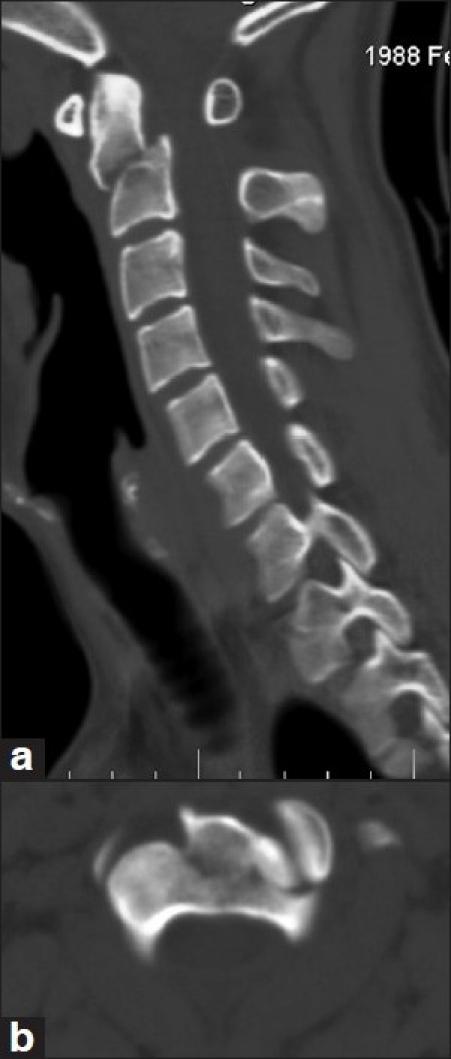

Anterior odontoid screw fixation or posterior C1-2 fusion techniques are routinely used in the treatment of Type II odontoid fractures, but these techniques may be inadequate in some types of odontoid fractures. In this new technique (Kotil technique), through a posterior bilateral approach, transarticular screw fixation was performed at the non-dominant vertebral artery (VA) side and posterior transodontoid fixation technique was performed at the dominant VA side. C1-2 complex fusion was aimed with unilateral transarticular fixation and odontoid fixation with posterior transodontoid screw fixation. Cervical spinal computed tomography (CT) of a 40-year-old male patient involved in a motor vehicle accident revealed an anteriorly dislocated Type II oblique dens fracture, not reducible by closed traction. Before the operation, the patient was found to have a dominant right VA with Doppler ultrasound. He was operated through a posterior approach. At first, transarticular screw fixation was performed at the non-dominant (left) side, and then fixation of the odontoid fracture was achieved by directing the contralateral screw (supplemental screw) medially and toward the apex. Cancellous autograft was scattered for fusion without the need for structural bone graft or wiring. Postoperative cervical spinal CT of the patient revealed that stabilization was maintained with transarticular screw fixation and reduction and fixation of the odontoid process was achieved completely by posterior transodontoid screw fixation. The patient is at the sixth month of follow-up and complete fusion has developed. With this new surgical technique, C1-2 fusion is maintained with transarticular screw fixation and odontoid process is fixed by concomitant contralateral posterior transodontoid screw (supplemental screw) fixation; thus, this technique both stabilizes the C1-2 complex and fixes the odontoid process and the corpus in atypical odontoid fractures, appearing as an alternative new technique among the previously defined C1-C2 fixation techniques in eligible cases.

前路齿突螺钉固定或后路C1-2融合技术常用于治疗Ⅱ型齿突骨折,但这些技术在某些类型的齿突骨折中可能并不适用。在这项新技术(科蒂尔技术)中,通过双侧后路入路,在非优势椎动脉(VA)侧进行经关节螺钉固定,并在优势VA侧进行后路经齿突固定技术。通过单侧经关节固定实现C1-2复合体融合,并通过后路经齿突螺钉固定进行齿突固定。一名40岁男性机动车事故患者的颈椎计算机断层扫描(CT)显示为Ⅱ型斜形齿突骨折且向前脱位,经闭合牵引无法复位。术前,通过多普勒超声发现该患者右侧VA为优势侧。他接受了后路手术。首先,在非优势(左侧)侧进行经关节螺钉固定,然后将对侧螺钉(补充螺钉)向内侧并朝向齿突尖部置入以实现齿突骨折固定。分散植入松质骨自体骨进行融合,无需结构性骨移植或钢丝固定。患者术后颈椎CT显示,经关节螺钉固定维持了稳定性,后路经齿突螺钉固定完全实现了齿突的复位和固定。患者处于随访的第六个月,已实现完全融合。通过这项新的手术技术,经关节螺钉固定维持了C1-2融合,同时通过对侧后路经齿突螺钉(补充螺钉)固定了齿突;因此,在符合条件的病例中,这项技术既稳定了C1-2复合体,又固定了齿突和齿突体,在先前定义的C1-C2固定技术中,它是一种可供选择的新技术。